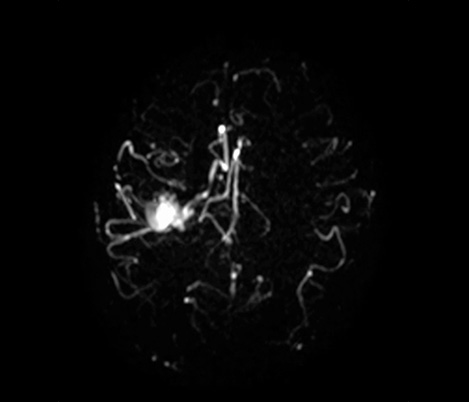

De la colaboración El Dr. Tetsuya Yoneda, Universidad de Kumamoto, Japón, habla sobre su colaboración con Philips en una técnica llamada SWIp desarrollada para la imagenología ponderada por susceptibilidad.

...a la práctica clínica El Dr. Chip Truwit, Centro Médico del Condado de Hennepin, Minneapolis, EE. UU. explica cómo SWIp se convirtió en una parte integral de todas las exploraciones de traumatismo por resonancia magnética.